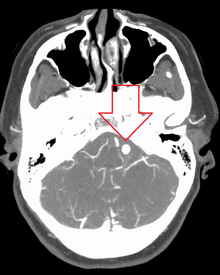

Ruptured 7mm left vertebral artery aneurysm resulting in a subarachnoid hemorrhage as seen on a CT scan with contrast

Diagnosis of a ruptured cerebral aneurysm is commonly made by finding signs of subarachnoid hemorrhage on a computed tomography (CT) scan. If the CT scan is negative but a ruptured aneurysm is still suspected based on clinical findings, a lumbar puncture can be performed to detect blood in the cerebrospinal fluid. Computed tomography angiography (CTA) is an alternative to traditional angiography and can be performed without the need for arterial catheterization. This test combines a regular CT scan with a contrast dye injected into a vein. Once the dye is injected into a vein, it travels to the cerebral arteries, and images are created using a CT scan. These images show exactly how blood flows into the brain arteries.[citation needed]